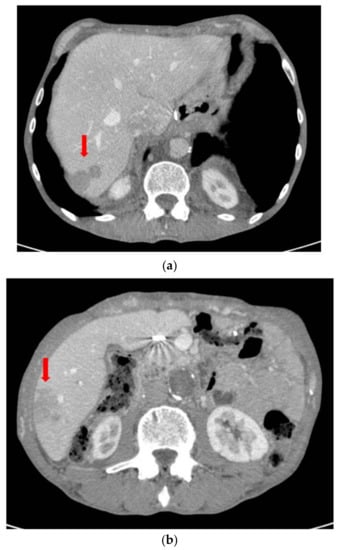

2. Case Report